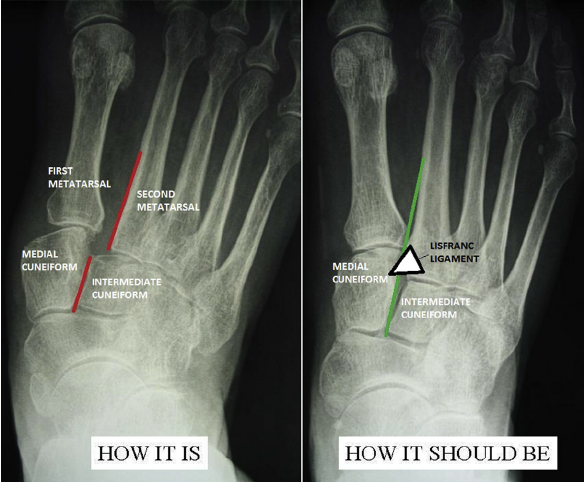

What investigations are required for a suspected Lisfranc injury?

Signs of Lisfranc injury are subtle on radiographs; state at least one possible sign